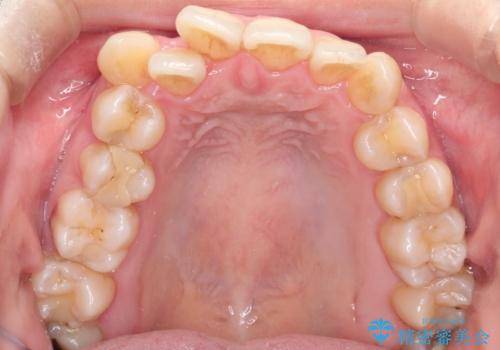

ガタガタの抜歯矯正を裏側ワイヤーを使っての目立たない矯正

- 八重歯とガタガタを主訴に来院されました。

目立たないワイヤー矯正を希望されたので、上下左右のはを1本ずつ抜歯して、ハーフリンガル(上顎だけ裏側)にて矯正をすることにしました。